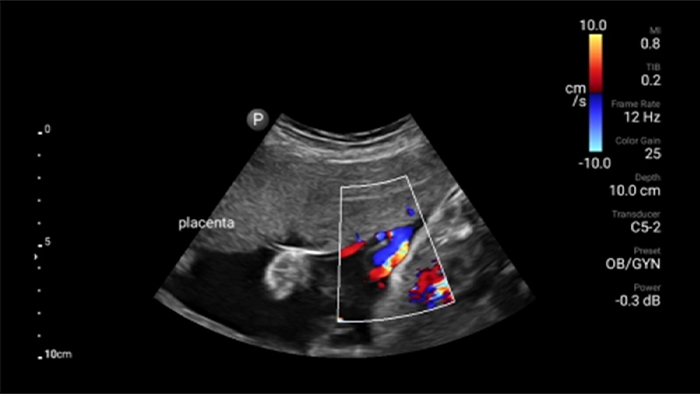

Ultrasonido renal focalizado